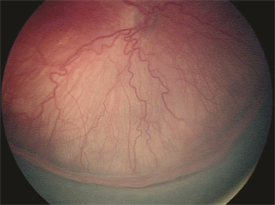

Figure 1.

Infants of low birthweight (under 1500 grams or 3.3 lbs.) and gestational age (30 weeks or less)—as well as infants deemed higher risk by the neonatologist (due to multiple births, oxygen exposure after birth, etc.)— are screened with either bedside eye exams or digital pictures of the back of the eye (retina), which are then reviewed by a physician experienced in the diagnosis and treatment of ROP. Once ROP progresses to a certain level of severity (Figure 1), treatment is recommended. Treatment is most often required between 34 to 38 weeks of gestation.